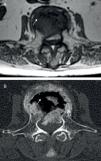

Consultó por lumbalgia de características inflamatorias de 4 semanas de evolución, sin antecedente traumático, fiebre ni síntomas constitucionales. La radiografía lateral de columna lumbar objetivó una fractura-aplastamiento de L3 con fenómeno del vacío intravertebral (FVI), sugeriendo una osteonecrosis vertebral (ON). La tomografía computarizada (TC) y la resonancia magnética (RM) confirmaron este diagnóstico (figs. 1-3). Se realizó fijación quirúrgica de la zona. El estudio histológico objetivó signos de necrosis ósea avascular: tejido óseo trabecular con extensas zonas de necrosis; espacio medular con proliferación de tejido de granulación, escasos elementos hematopoyéticos, necrosis y detritus celulares.

El FVI, aunque no es patognomónico, es el signo radiológico más característico de esta entidad y el que suele sugerir el diagnóstico3,4. Este signo traduce la presencia de gas dentro del hueso (fundamentalmente nitrógeno) originado en tejidos adyacentes. El FVI puede observarse en el estudio radiológico, en forma de una imagen radiolucente lineal o en media luna situada generalmente adyacente al platillo vertebral superior, que aparece o se intensifica con la extensión, y disminuye o incluso llega a desaparecer con la flexión de la columna. En ocasiones es mínimo, pudiendo en estos casos ser detectado por TC o RM debido a su mayor sensibilidad.